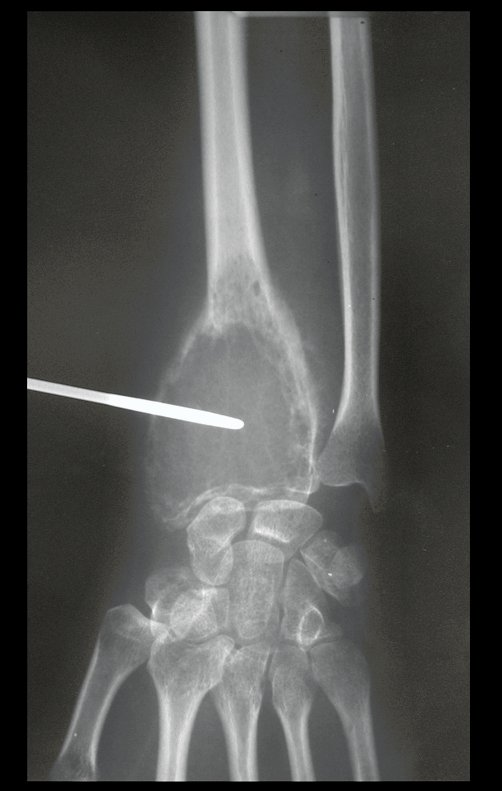

O estudo de ressonância magnética mostra lesão de rarefação óssea, com áreas de necrose, erosão, insuflação e fratura infracção da cortical, com deformidade e afundamento da superfície articular (figuras 25 a 36).

Com este estudo, confirmamos a agressividade local do tumor, e a grande destruição da extremidade distal do rádio esquerdo, com fratura por infracção, deformidade articular e encurtamento do rádio. Nesta situação o tratamento intralesional deve ser contraindicado, devido à alta possibilidade de recidiva local, além da perda da função. Oncologicamente está indicada a ressecção segmentar do rádio, e reconstrução do punho. A artrodese pode ser uma alternativa, mas preferimos preservar a função e a anatomia do punho, sempre que possível. Neste caso, optamos por reconstruir com enxerto autólogo não vascularizado, obtido do segmento proximal da fíbula ipsilateral, que mimetiza melhor o rádio.